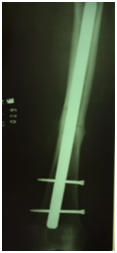

We report a case of bilateral femoral fracture in a patient after 7 years of treatment with alendronate at a dose of 70 mg weekly. The patient was a 67 y.o. female with no history of any comorbidity such as diabetes, alcohol abuse, smoking, chronic use of glucocorticoids or others. She fell from her own height in March 2014, resulting in a transverse femoral shaft fracture of the left femur (Figure 1A), treated with a blocked anterograde intramedullary nail (Figure 1B & 1C). In June 2016, she suffered a contralateral short oblique femoral fracture with no history of direct trauma, presumably with a torsional mechanism - rotation around the body axis (Figure 2A). The treatment of choice was also a blocked anterograde intramedullary nail (Figures 2B & 2C). We can observe in Figures 1 & 2 the absence of compromised trabecular bone or thinning of cortical bone, corroborating the probable pathophysiology behind bisphosphonate-associated fractures - decreased bone remodelling - and not osteopenia/osteoporosis.

Figure 2A Right femoral anteroposterior radiograph – Simple short oblique tract fracture with cortical thickening. 2B & 2C Postoperative radiography – anterograde blocked nail right femur.